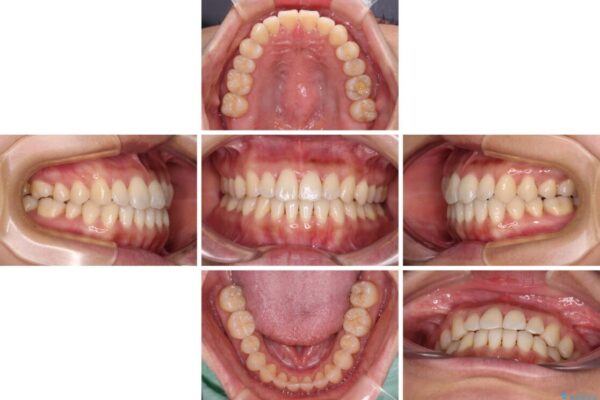

前歯のデコボコで前方に出ていることを気にして来院された患者様です。

上顎前歯が捻れて前方に飛び出しており、下顎前歯もそれに沿うようにデコボコとなっていました。

IPR(歯と歯の間を削る処置)によりスペースを獲得して上下顎前歯のデコボコを改善し、飛び出している前歯が引っ込むように設定し、インビザラインにて矯正治療を行うこととしました。

治療前

• 【モニター】前歯のデコボコをインビザラインで改善 治療前画像